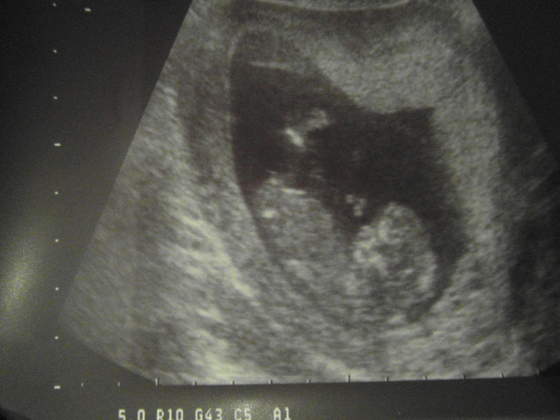

Mój bobasek 12+3 z wymiarów ( termin na 1.09) zobaczymy jak będzie